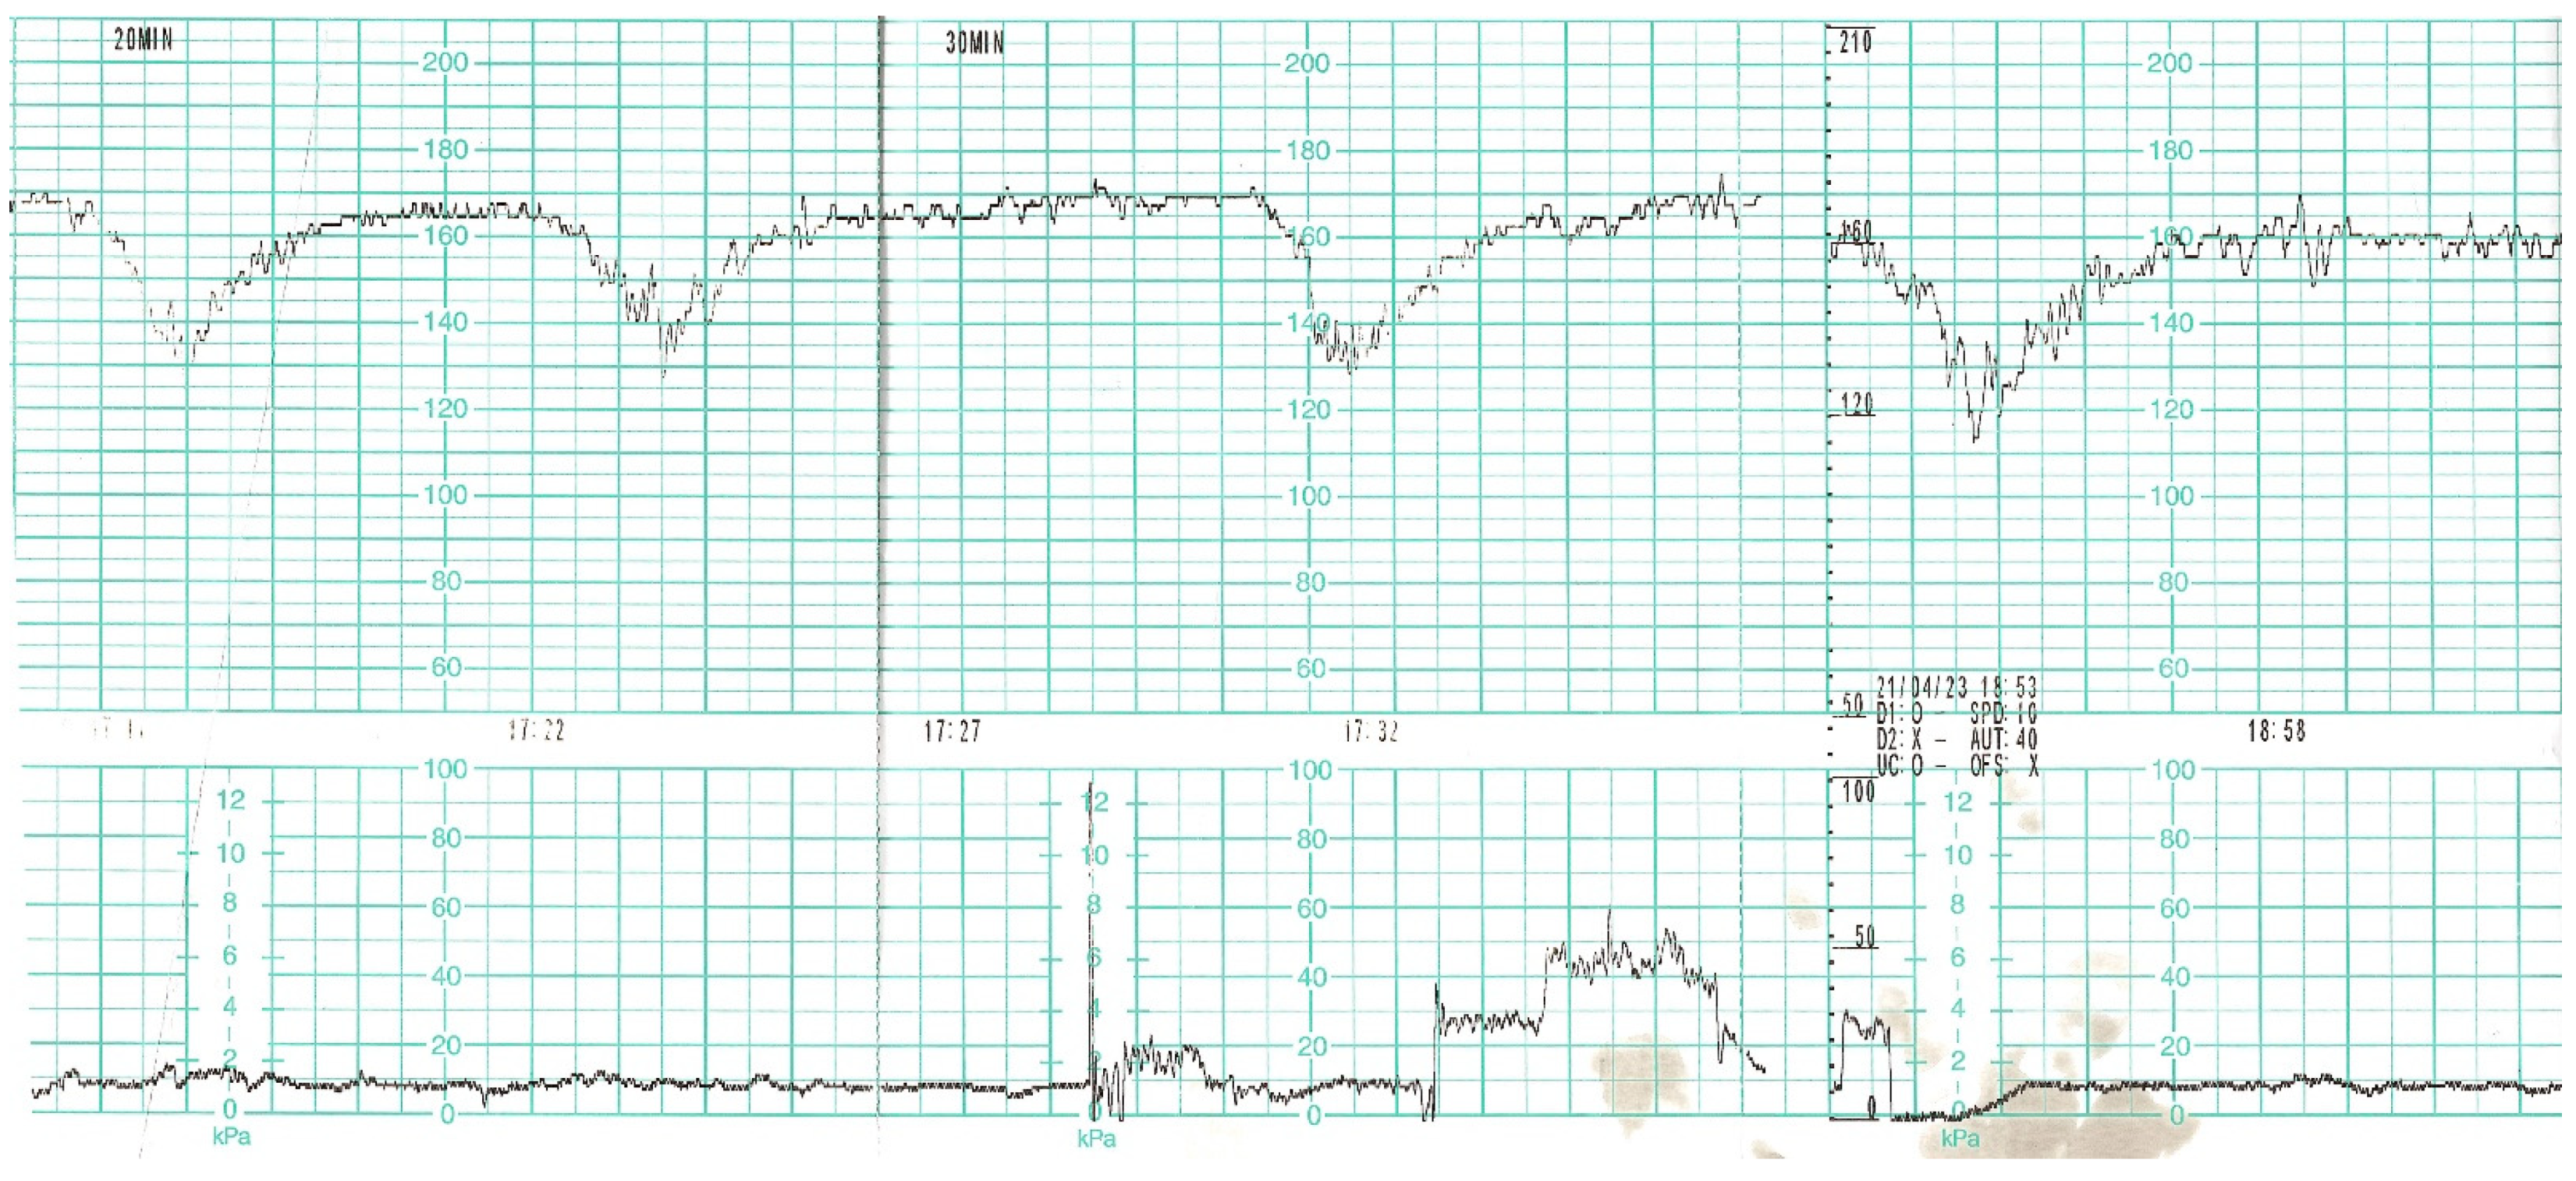

On the day of caesarean section, the patient’s vital parameters were: BP 130/80 mmHg, HR 110 bpm, Sat. 96%, breaths 20/min. Laboratory tests showed persistent abnormal clotting parameters. The drainage from the pelvis was 800 mL of blood, and in the control abdominal ultrasound examination the subcutaneous haematoma was observed. Due to the above, the patient was qualified to the relaparotomy and pelvic revision. During the procedure, another 2 g of fibrinogen, 2 units of platelet concentrate and 2 units of packed red blood cells were given. During the next two days, the patient was monitored in a postoperative room. Stable laboratory test values were obtained. Table 1 summarises the results of the patient’s examinations. A CT scan of the chest was performed. Massive converging zones of bubble densities in the type of frosted glass and paving stones, suggesting viral inflammation (typical for SARS-CoV-2 infection) were visible—see Figure 4 and Figure 5. Due to the gradually increasing respiratory failure (saturation 90%, and hypoxia—pO2 54 mmHg in a control arterial probe), high-flow nasal oxygen therapy was started. The satisfactory effect was not achieved. Sedation, intubation, and mechanical ventilation was initiated. After initial stabilisation the patient was transferred to the Intensive Care Unit, where she stayed for 8 days until improvement in oxygenation was achieved. She was successfully extubated and transferred to the Maternity Ward, from where she was discharged on the 22nd day of hospitalisation in good general condition.

Figure 4.

Chest Computed Tomography (HRCT).

Figure 5.